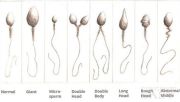

| 07:43, 16 באוגוסט 2023 | זרעונים1.jpg (קובץ) |  |

28 קילו־בייטים | Motyk | 1 | |